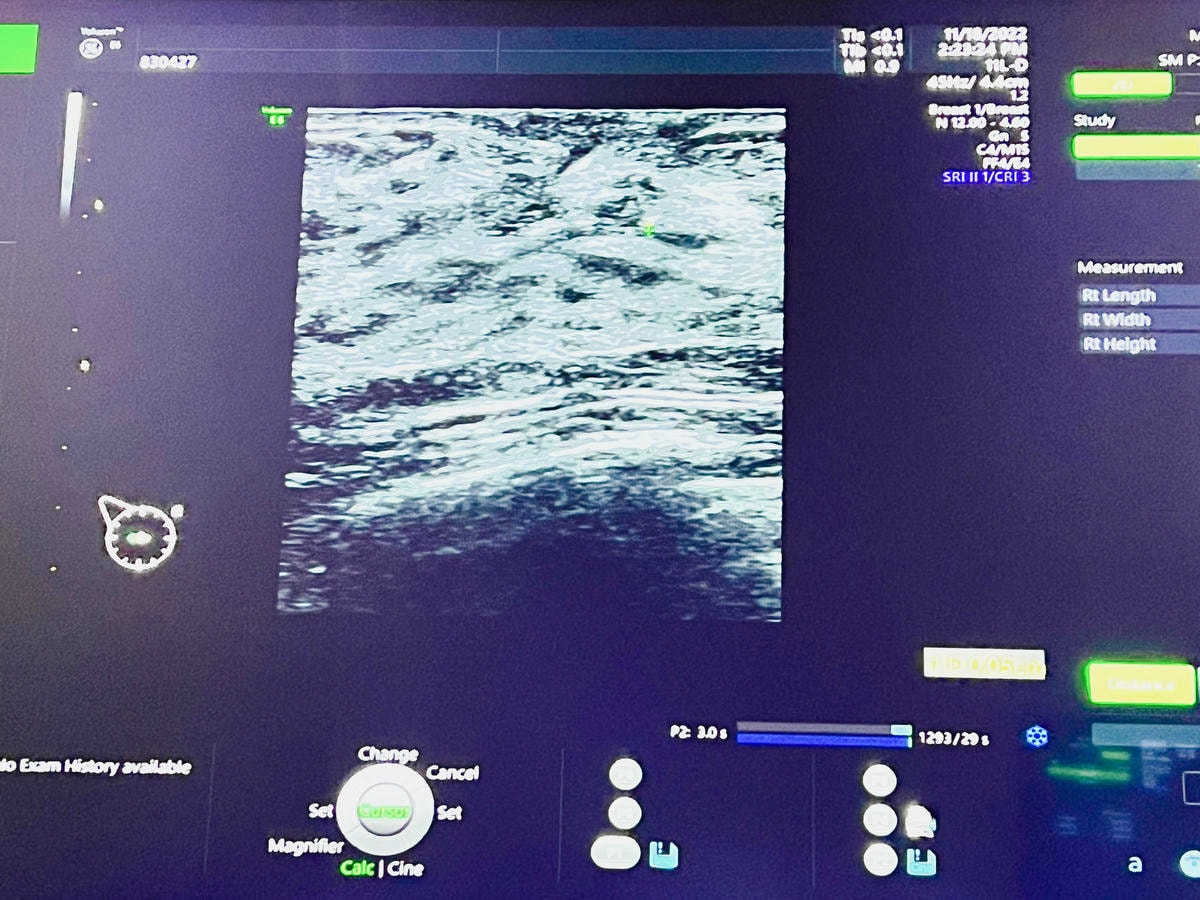

高層次乳房超音波是使用高頻率的音波來查看組織的波動,各年齡層都適合使用

再搭配4D精密高畫質儀器,以多種角度操作探頭,來檢測乳房是否有異狀

對於腫瘤、腺瘤、跟囊腫等病灶,也能找出具體的位子、形狀、及大小

這是一種非侵入性、無放射性的精密檢查

開始檢查時,健檢師會擠上一些凝膠與探頭在乳房按壓的方式來照超音波

再利用不同的角度檢查每個位置的狀況,同時也會細心介紹乳房內的組織

躺在床上,眼前有螢幕是會投射影像,方便健檢師在講解時

我們也可以清楚了解自身的乳房狀況